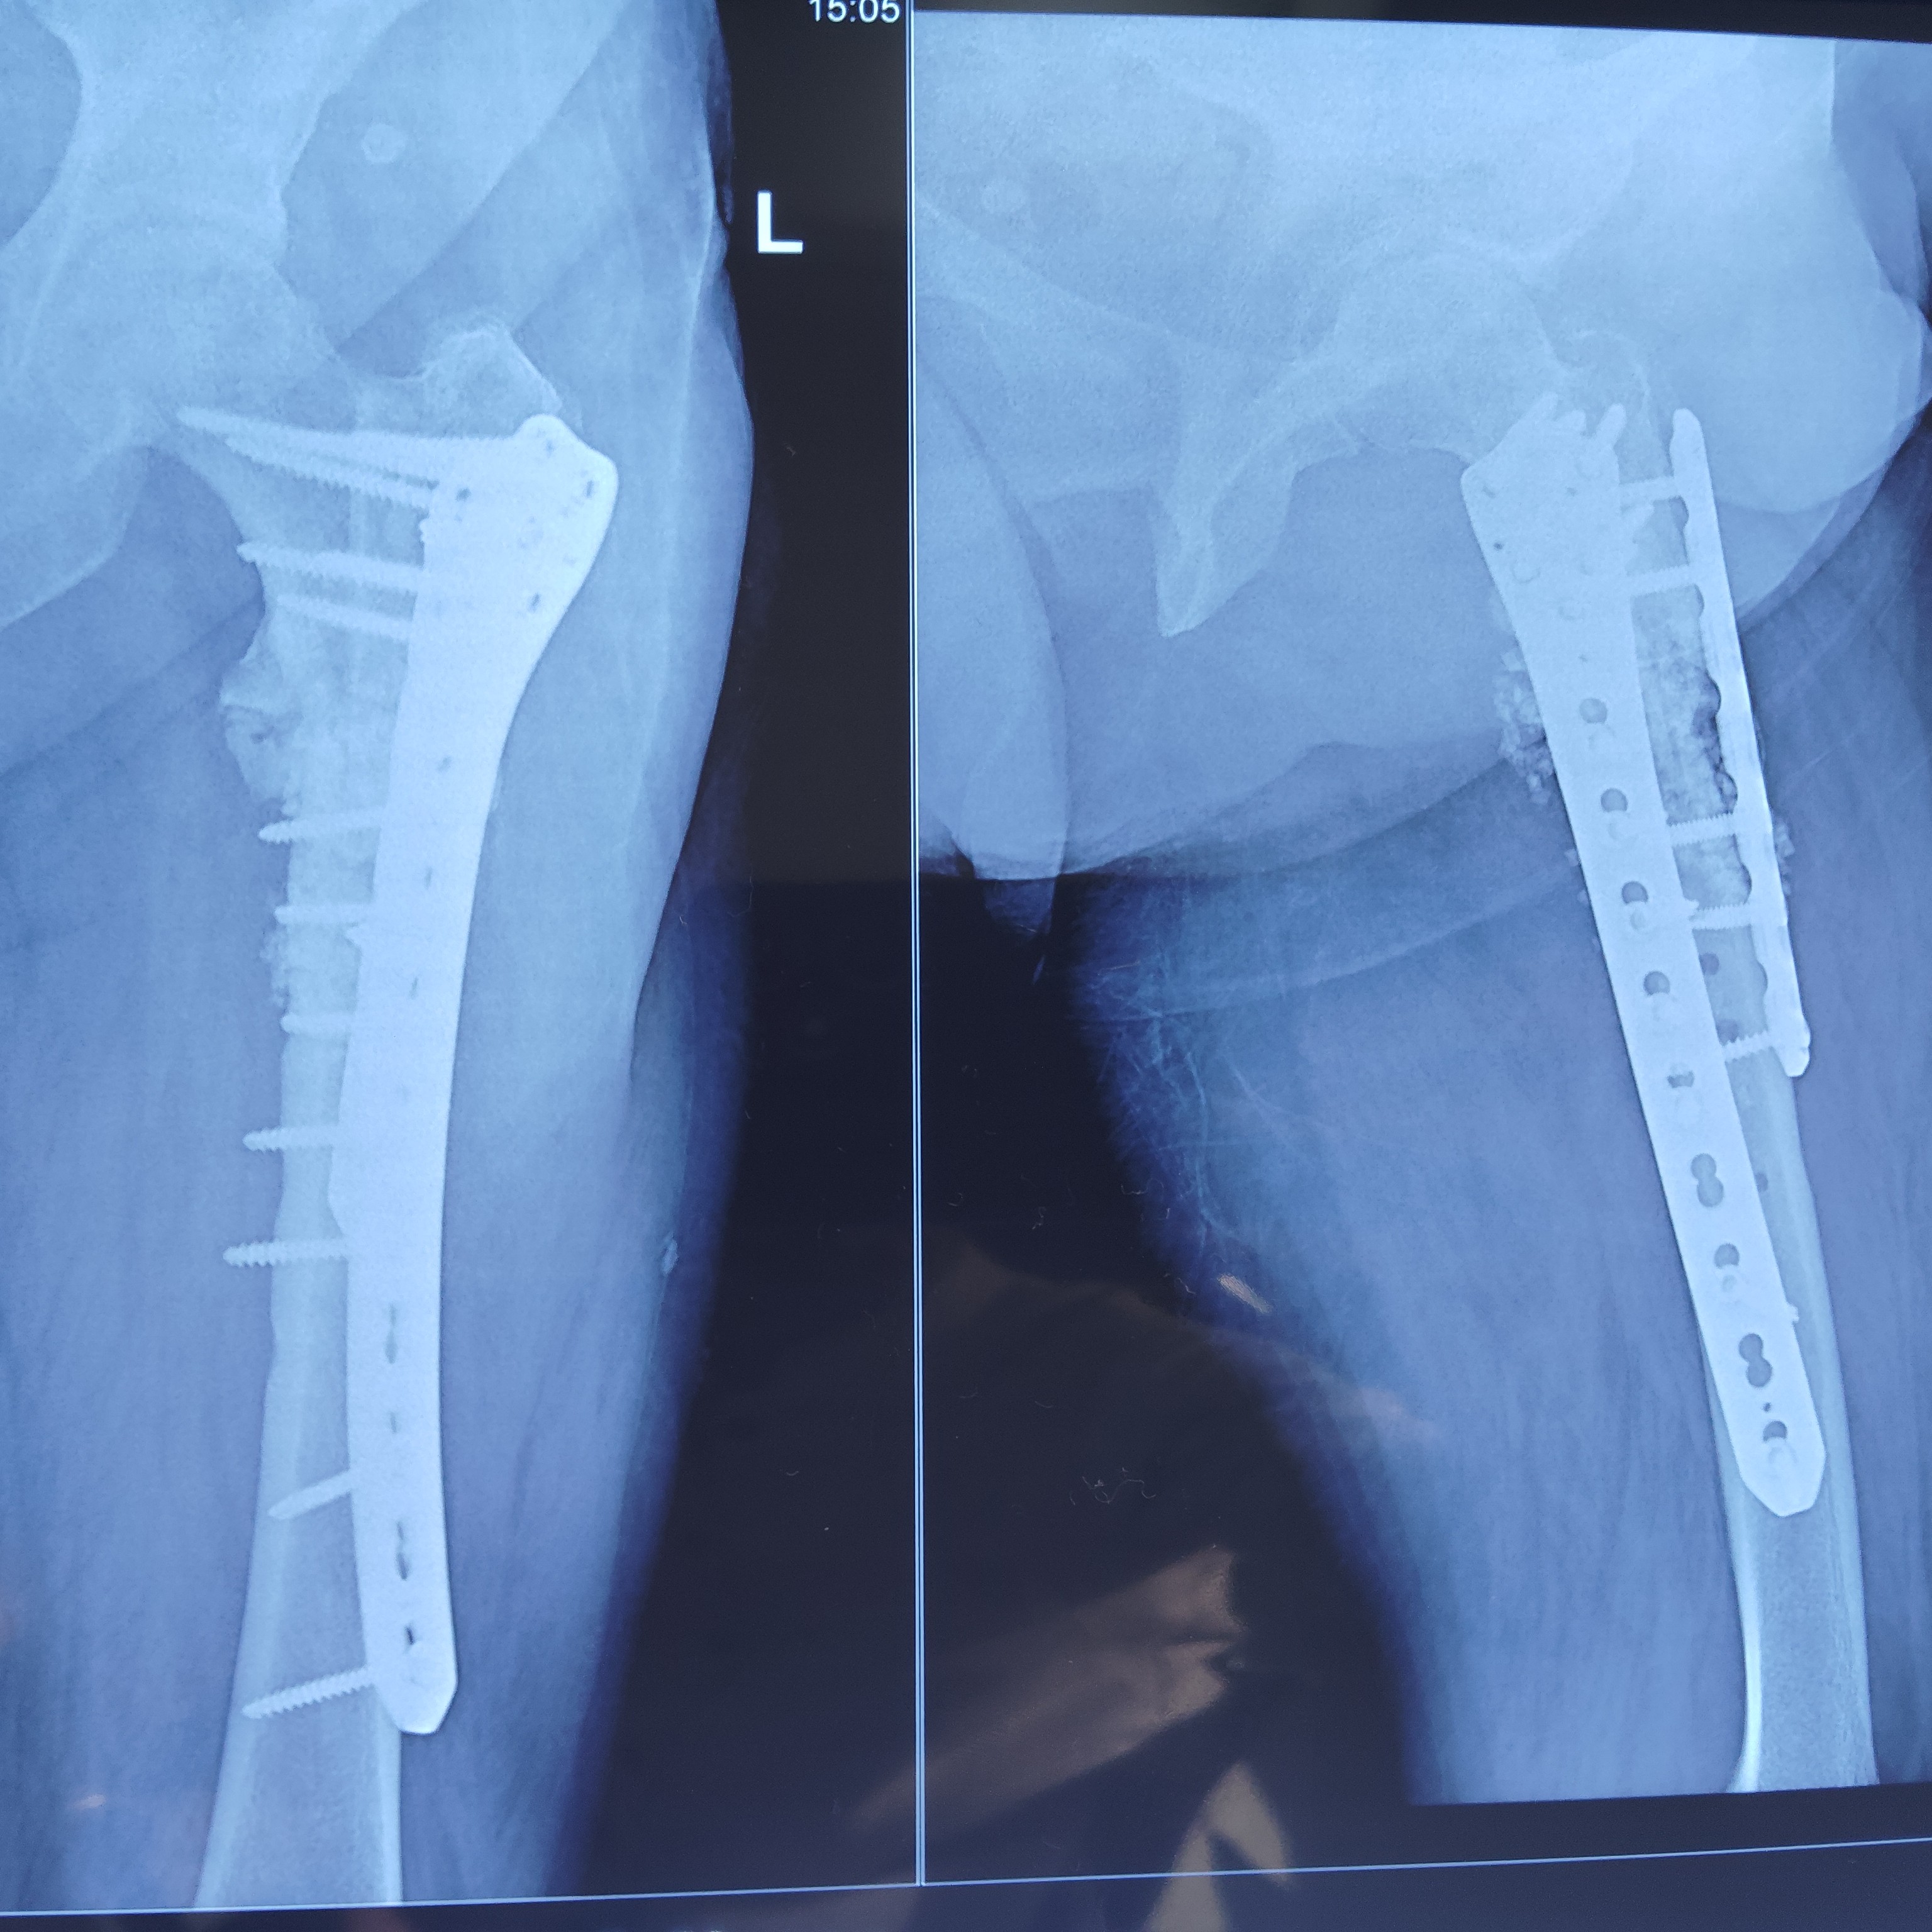

Successfully united long standing difficult non union atypical fracture proximal femur